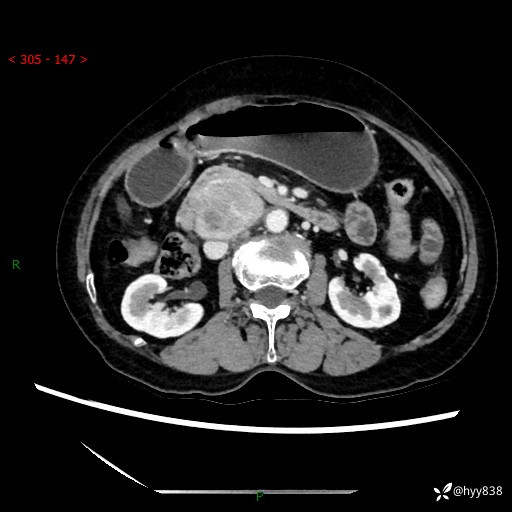

71岁/女,腹痛1月余。腹膜后肿物,间质瘤 VS 副节瘤 VS 平滑肌肉瘤---(有结果)

【患者信息】:71岁/女

【主诉】:腹痛1月余

【检查】:腹部CT增强扫描(外院CT平扫)